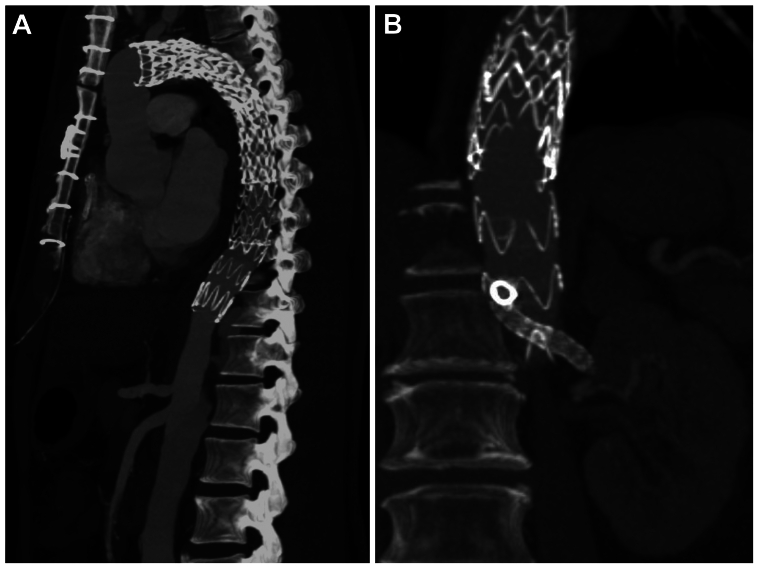

Fig 5.

Computed tomography angiograms demonstrating thoracic endovascular aortic repair (TEVAR) extension through the laser-fenestrated septum into the true lumen in patient 1 (A), and the bridging stent from the physician-modified endograft to the left renal artery through the laser-fenestrated septum in patient 2 (B).